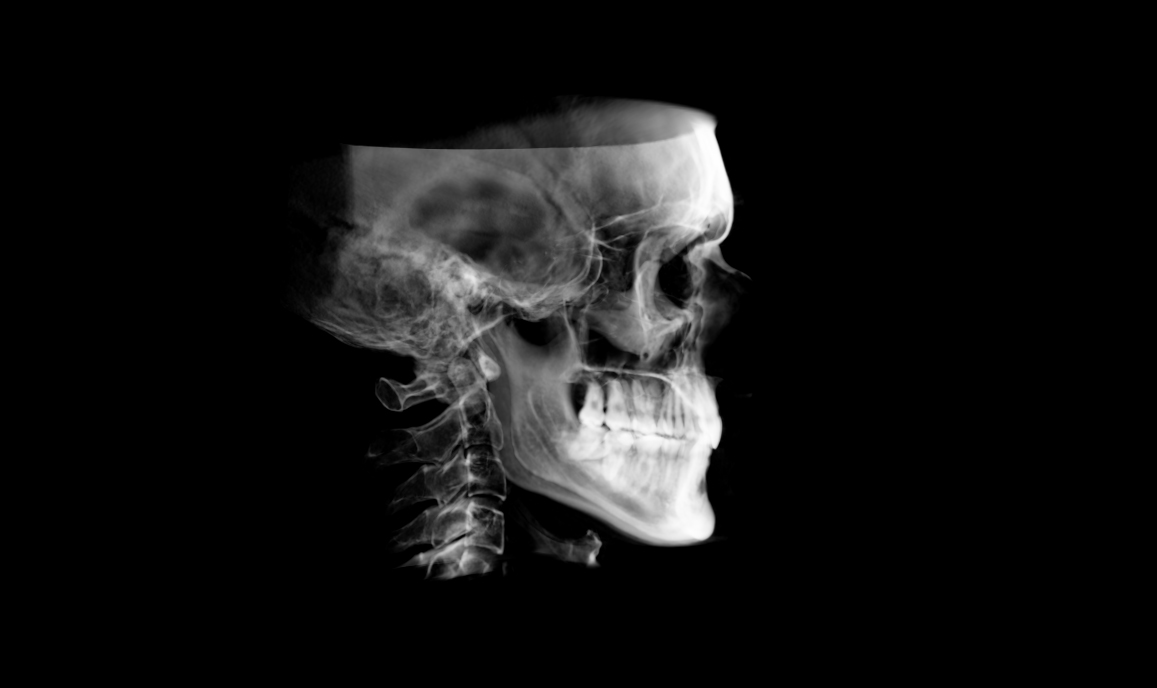

Completed last turn on MARPE on 9th Jan. Total (net, as I went back and forth a bit towards the end) 65 turns = ~5.42mm lateral skeletal expansion of upper jaw going by the device design. IMW (Intermolar width) increased by 7mm from 31 – 38mm.

CBCT: